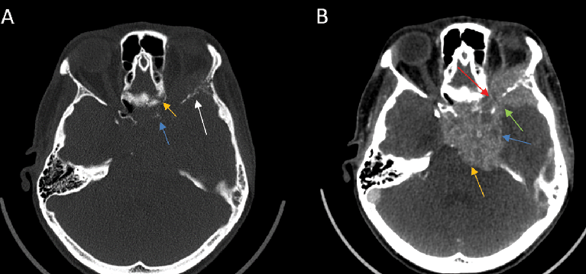

2) Enlargement and/or Erosion of Neural Foramina or Canals (Figs. 2–3). Perineural Spread (PNS) can manifest radiologically as morphological alterations of neural passageways, characterized by foraminal or canal enlargement secondary to neural expansion. This is a delayed finding, as the normal nerve is smaller than the foramen, and it has ample time to enlarge before bone destruction becomes evident. On imaging studies, this enlargement of foramina typically presents as bilateral asymmetry. However, isolated foraminal enlargement demonstrates limited specificity, as it may represent benign pathological processes or anatomical variants. The presence of concurrent foraminal or canal erosive changes provides stronger radiological evidence for malignant processes, particularly PNS, thereby carrying greater diagnostic significance [29]. Enlargement or erosion of neural foramina or canals is more effectively visualized on CT compared to MRI.

3) Obliteration of Fat Planes and pterygopalatine fossa (Fig. 4 C). In Perineural Spread (PNS), tumor invasion can disrupt and replace the normal fat planes surrounding nerves, which serve as a natural barrier visible on imaging. This obliteration, often seen as a loss of the normal hypodense fat signal on CT or the hyperintense fat signal on MRI T1 sequences, indicates tumor infiltration or extension, aiding in the diagnosis of PNS [2].